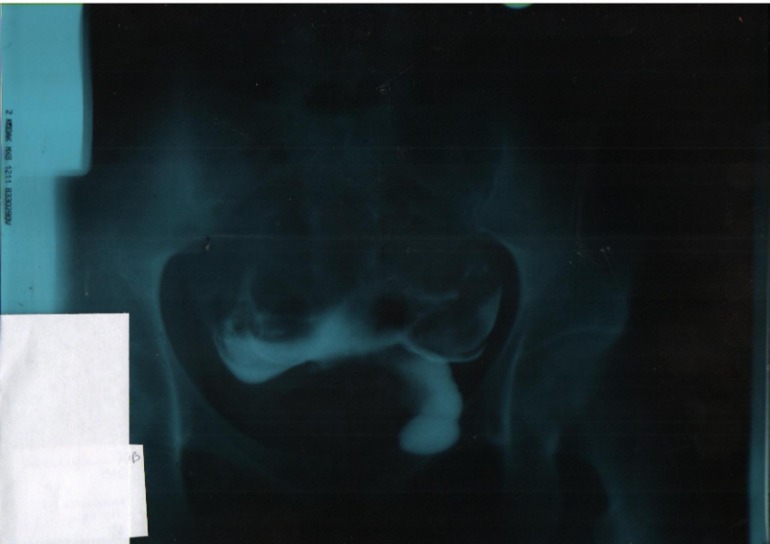

Всем привет. Может здесь кто-нибудь описать результат ГСГ. Я не согласна с диагнозом, поставленным рентгенологом, а сама не могу разобраться в этой каляке-маляке

, в интернете сколько смотрела снимки, у всех все четко, и матку видно и трубы, а меня не пойми что. Прокомментируйте пожалуйста кто понимает.

Первый снимок - лежа, второй - стоя.

как то ваши трубы разбросаны по брюшной полости, скорее всего спайки! да и выходящего контраста я не вижу! плохо снимок сделали, на нем даже матку как таковую плохо видно! а что в заключении написали?

Согласна что снимки плохие, и это уже второй раз у меня, оба раза почему-то вот так все размыто. Может у нас как-то не правильно делают, а в заключении: матка смещена влево, правая труба проходима, левая нет.

одна труба проходима сто процентов..а вот вторая судя по всему нет..жидкость пошла в брюшную полость..и должно быть хотябы 4 снимка на сколько я помню..